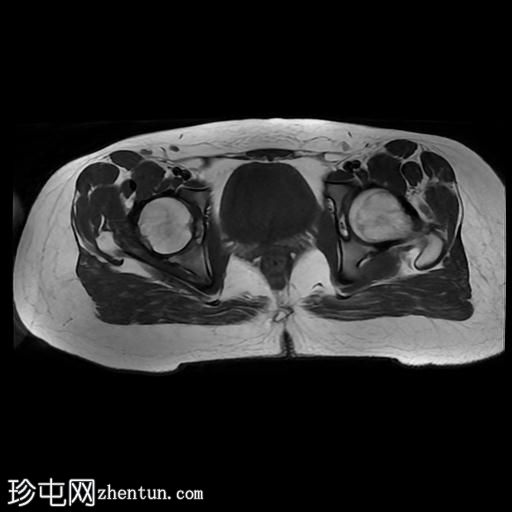

MRI

轴位T2加权像

脂肪抑制像

臀中肌髂骨起点处前侧全层撕裂,伴有充满液体的间隙,以及髂骨髓水肿。

MRI结果符合臀中肌近端髂骨起点处全层撕裂的

影像

学表现。